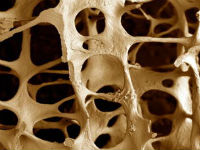

Csontritkulás - krónikus, progresszív szisztémás metabolikus csontbetegség karakter vagy külön klinikai szindróma bizonyos betegségek alapuló csökkentésére csontsűrűség és zavar normál szerkezetének. Ez ahhoz vezet, hogy a csont törékenysége és jelentősen megnövekedett törési kockázat a csontritkulásban szenvedő.

Bal mutatja normál szerkezetének a csont, és a megfelelő - a szerkezetét csontritkulás